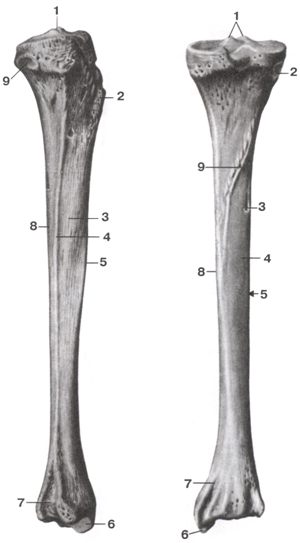

Анатомия фибулы: Подробные фотографии и схемы